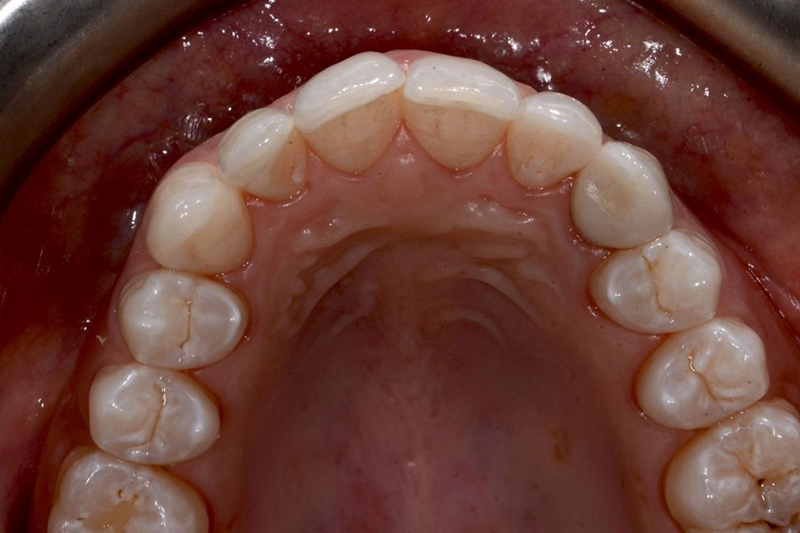

口内检查中,乳牙处可见大量角质化牙龈,整体口腔卫生状况良好(图5-7)。

Fig. 5: Intraoral frontal view

Fig. 6: Intraoral view: The discrepancy between upper canines and lateral incisors is clear. Note that the deciduous tooth is shorter than the contralateral, both at the occlusal and at the gingival side.

Fig. 7: Magnification of the deciduous tooth: A wide amount of keratinized gingiva is shown.